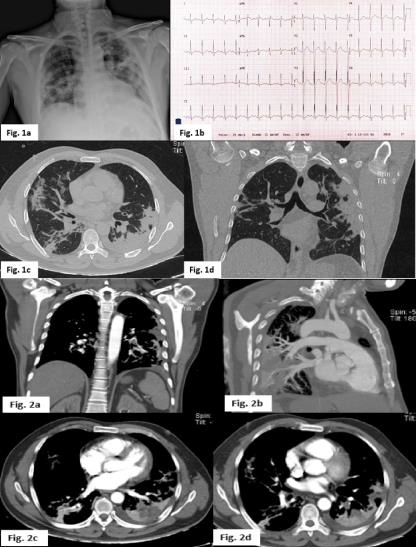

Wells DVT score 3 points. Wells PE score 9 points. Geneva score 15 points. PERC score 4 points. US Doppler reporting a thrombus in the left femoral vein. Initial laboratory workout reported D-Dimer 4,700 ug/L, ferritin 2535 ng/ml, PCR 270 mg/l, fibrinogen 934 mg. CPK / MB 106/11 U/L. CBC: Hgb 12.8 gr, leukocytes 24,400, platelets 205.000. BNP 10 pg./ml. PaO2/FIO2 = 142 mmHg. EKG: sinus tachycardia, SQ3T3 pattern, as well as late R in AVR suggestive of dilatation of the right ventricle. No evidence of growth of heart chambers (Figure 1b). Chest radiograph showed bilateral consolidation of peripheral distribution, predominantly left basal, classified on the ERVIN scale as severe (Figure 1a). Contrast chest angiotomography showed hypodense-filling defect in the subsegmetary branch for the upper basal and posterior basal segment of the left lung, with the presence of a lung consolidation area. Furthermore, a hypodense image was also observed, of triangular morphology at the pleural base which did not present reinforcement in the contrasted phase in relation to the zone of pulmonary infarction (Figure 2a), in lung window axial Multiple pulmonary consolidations of peripheral distribution were observed, related to the typical SARS CoV-2 pneumonia, specifically type C pattern, with a severe degree involvement (Figure 1c and 1d). Therefore, the patient is considered a COVID-19 suspected case and nasopharyngeal sample for real-time PCR was performed with was later reported positive.

Figure 1: a Chest radiograph in anteroposterior projection with multiple ground glass images and bilateral consolidation. Figure 1b SQ3T3 pattern electrocardiogram as well as late R in AVR suggestive of dilatation of the right ventricle. Figure 1c and 1d Axial section lung window: Multiple pulmonary consolidations of peripheral distribution are observed in relation to the typical pattern with SARS CoV-2 pneumonia with a type C pattern, with a degree of severe involvement. Figure 2a and 2b. Contrast-phase computed tomography with hypodense bundle defect in the upper basal segment and the left posterior basal segment. Figure 2b and 2c Hypodense image, with pleural based triangular morphology that does not present reinforcement in the contrasted phase in relation to the zone of pulmonary infarction.